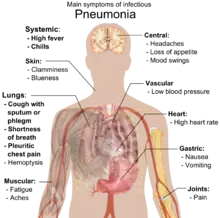

Клиническая картина

«Типичная» пневмония характеризуется резким подъёмом температуры, кашлем с обильным выделением гнойной мокроты и, в некоторых случаях, плевральной боли. При исследовании: укорочение перкуторного звука, жёсткое дыхание, усиленная бронхофония, усиленное голосовое дрожание, сначала сухие, а затем влажные, крепитирующие хрипы, затемнение на рентгенограмме. Такую пневмонию вызывают Streptococcus pneumoniae, Haemophilus influenzae, Escherichia coli, Klebsiella pneumoniae.

«Атипичная» пневмония характеризуется постепенным началом, сухим, непродуктивным кашлем, преобладанием в клинической картине второстепенных симптомов — головной боли, миалгии, боли и першения в горле, слабости и недомогания при минимальных изменениях на рентгенограмме. Этот тип пневмонии вызывают, как правило, Mycoplasma pneumoniae (микоплазменная пневмония), Legionella pneumophila (легионеллёзная пневмония), Chlamydia pneumoniae (хламидийная пневмония), Pneumocystis jirovecii (пневмоцистная пневмония).